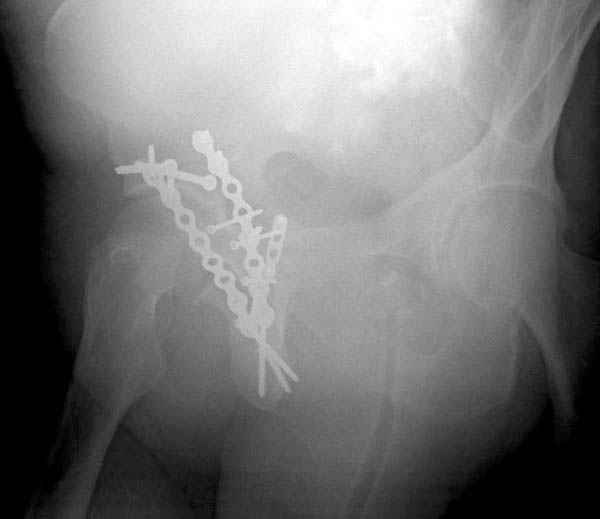

Дополнительно имеется перелом ацетабулума: задняя

колонна с полупоперечным переломом, и переломы костей лица.

На седьмой день зафиксирован перелом ацетабулума через задний доступ.

Имя     : 4 proximal hum +acetabulum.jpg

Тип     : image/jpeg

Размер  : 19494 байтов

Описание: отсутствует

Url     : http://weborto.net:8080/pipermail/ortho/attachments/20071129/c86944d4/attachment-0009.jpg

Имя     : 6 proximal hum +acetabulum iliac.jpg

Размер  : 19051 байтов

Url     : http://weborto.net:8080/pipermail/ortho/attachments/20071129/c86944d4/attachment-0010.jpg